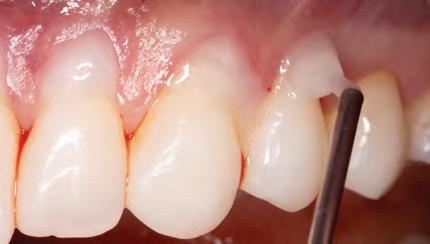

A 31-year-old woman presented with cosmetic concerns regarding her smile and requested a conservative enhancement. After clinical and radiographic analysis, digital 35mm photographs were taken and reviewed by the restorative clinician, technician, and surgeon (Fig 1). A digital impression was taken of the maxillary and mandibular arches using an intraoral scanner (Trios 3, 3Shape; Fig 2), and a smile design was developed with NemoSmile Design 3D software (Nemotec; Fig 3a). This allows for a facially driven smile frame to be created using reference lines of facial and smile proportions and natural teeth shapes and textures from the digital library (Fig 3b).

After developing the simulated mock-up, a 3D-printed resin model was created using CAD software (Fig 4a), and a clear PVS matrix (Exaclear, GC America) was fabricated to replicate the printed diagnostic wax-up using a nonperforated tray (Fig

Fig 1 Preoperative clinical views of a 31-year-old woman presenting with diastemas and limited tooth visibility. (top) Portrait. (center row) Intraoral views. (bottom row) Smile.

4b). This matrix was used to create an intraoral motivational mock-up with bis-acryl composite (Luxatemp Ultra, DMG). This additive mock-up provides the interdisciplinary team with an intraoral translation for evaluation (Fig 5). Upon evaluation of the digital smile frame and the clinical translation, it was determined that multiple esthetic and restorative requirements were necessary for an optimal biologic framework, and the interdisciplinary team determined the best sequence for these procedures. The patient was presented with the interdisciplinary treatment possibilities that included restoring the maxillary anterior teeth and premolars with a minimally

invasive preparationless procedure or with less conservative veneer preparations. The restorative materials discussed included injectable resin composites and ceramic (ie, feldspathic, pressable, machinable). For an optimal biologic framework and health, it was determined that connective tissue grafting would be necessary for treatment of the recessiontype defects on the maxillary left central and lateral incisors, canine, and premolars. The patient opted for the conservative preparationless composite veneers using the injectable resin technique followed by a connective tissue surgical procedure using the tunneling technique.